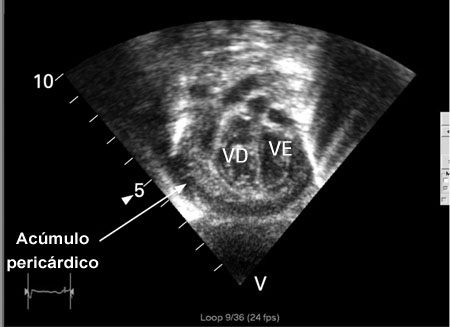

Ecocardiografia em um bebê com pericardite purulenta, mostrando uma coleção pericárdica. VE = ventrículo esquerdo, VD = ventrículo direito

Karuppaswamy V, Shauq A, Alphonso N. BMJ Case Reports 2009; doi:10.1136/bcr.2007.136564